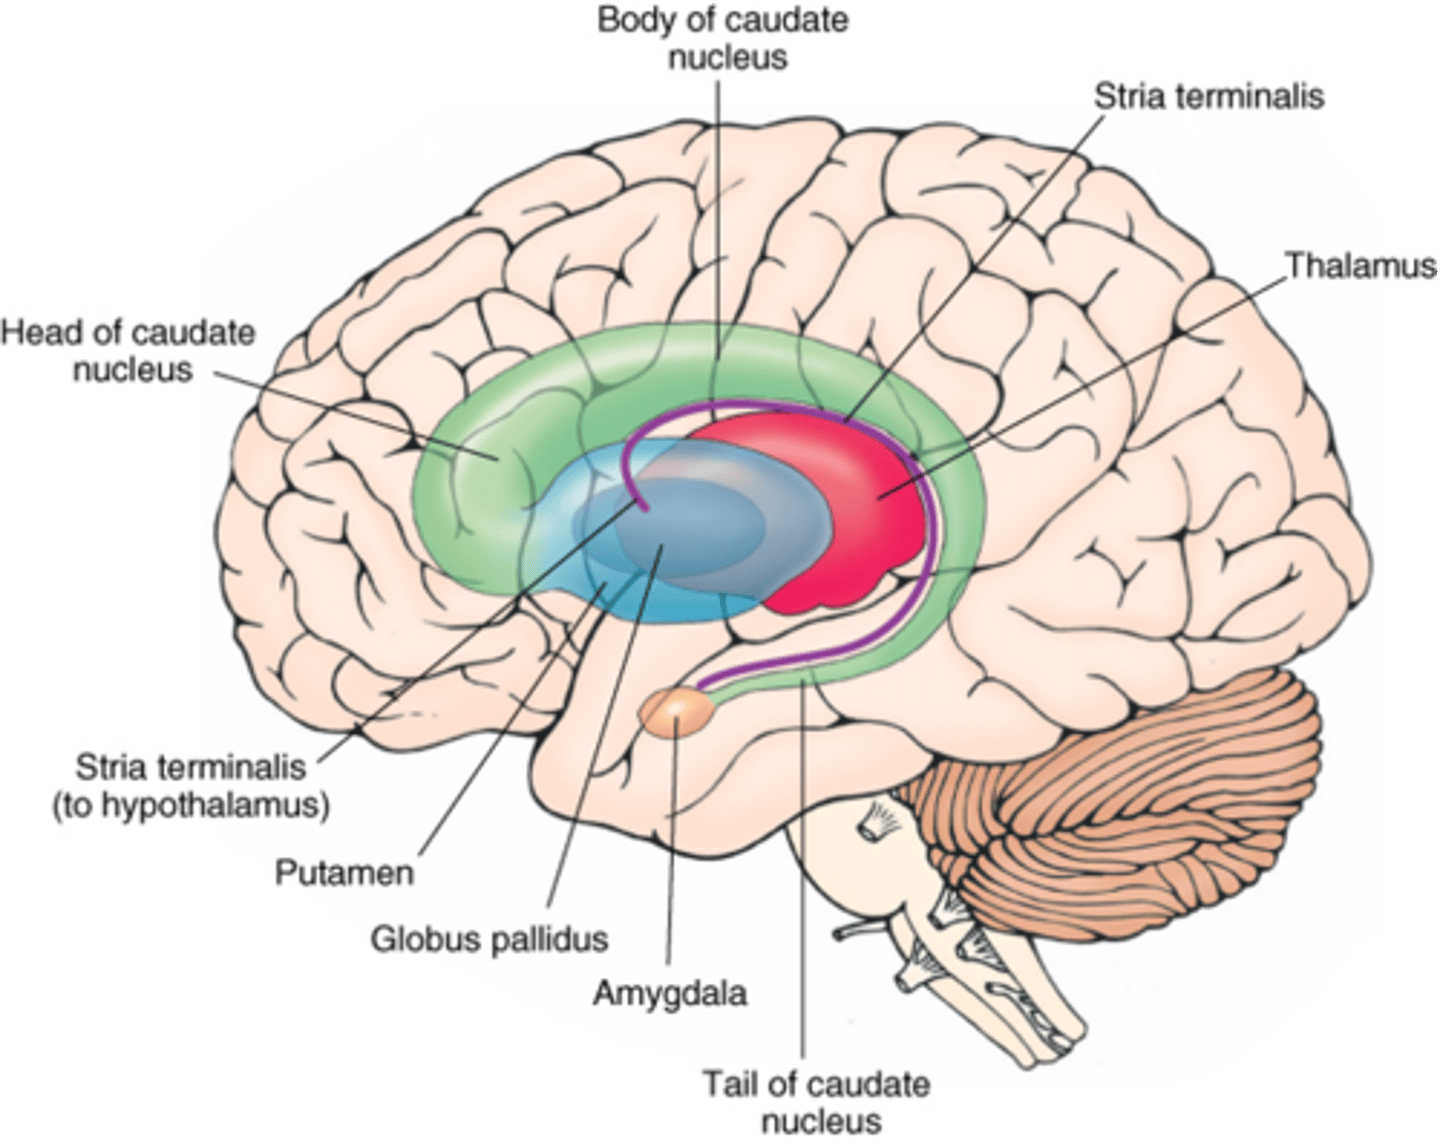

what cerebral gray matter structure is a collection of subcortical nuclei primarily involved in motor control?

basal ganglia

what cerebral gray matter structure has a gate-keeping mechanism for the initiation of motor movement (choosing which actions to allow and which to inhibit)?

basal ganglia

what cerebral gray matter structure has roles in motor learning, executive functions, behaviors, and emotions?

basal ganglia

what are the 3 parts of the basal ganglia? what runs between them?

1. caudate nucleus

2. putamen

3. globus pallidus

internal capsule

what part of the basal ganglia is the C-shaped structure that is most medial?

caudate nucleus

what part of the basal ganglia is medial to the putamen?

globus pallidus

the putamen and globus pallidus of the basal ganglia are collectively called the _______________ nucleus

lentiform